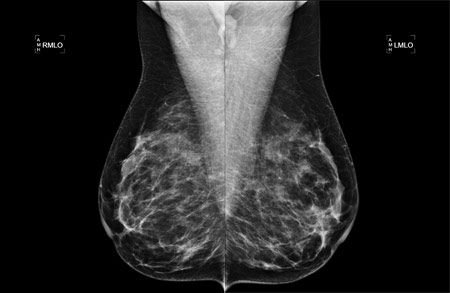

Mammography (also known as a mammogram procedure) is an examination of the breast using low dose X-rays. Most medical experts agree that successful treatment of breast cancer is often linked to early diagnosis, and mammography is considered the most effective tool for early breast tumor detection. It plays a central role in the early detection of breast cancer, as it can show changes in the breast up to two years before a patient or physician can feel them.

Mammograms are specialized X-ray images of breast tissue designed to detect cancer and other alterations. They serve two primary purposes:

Digital mammography, or 2D mammography, uses detectors that convert X-rays into electrical signals. These electrical signals produce images of the breast that can be seen on a computer screen. The radiologist is able to change the magnification, orientation, brightness, and contrast of these images.

3D mammography, or Tomosynthesis mammography, is an advanced form of breast imaging where images are acquired in 1 mm “slices” which are then reconstructed into a 3D image. The acquisition of many images in different angles provides more information per mammogram for radiologist interpretation. The positioning, compression, and radiation dose are equivalent to that of a traditional 2D mammogram.